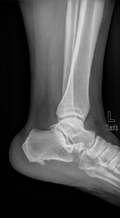

Артрография

Описание услуги - Артрография

Артрография осуществляется наметить суставы и связки. Краситель вводится в сустав и рентгеновские лучи приняты с целью выявления любых травм.

Типичные осложения:Повреждение суставов, инфекции, кровотечения, или аллергическая реакция на краску.